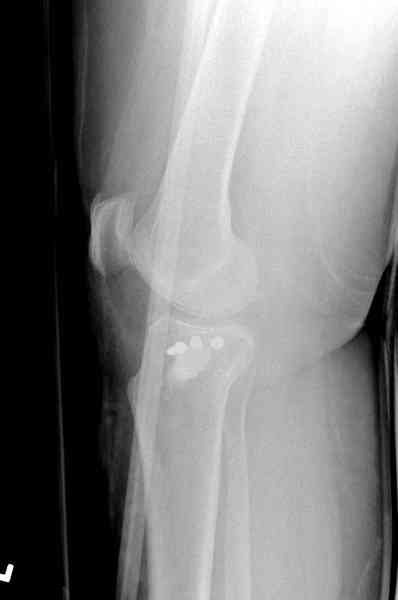

Из медиального окна можно приподнять латеральную

импрессию. Фиксация тремя параллельными шурупами в

эпифизарной части над импрессией. Создается крыша,

которая предупредит коллапс. На образовавшуюся полость - костная пластика из аутокости или синтетический заменитель. Мы применяем Osteoset в 4-5 мм диаметре таблеточки или иньекционную форму Prodens.